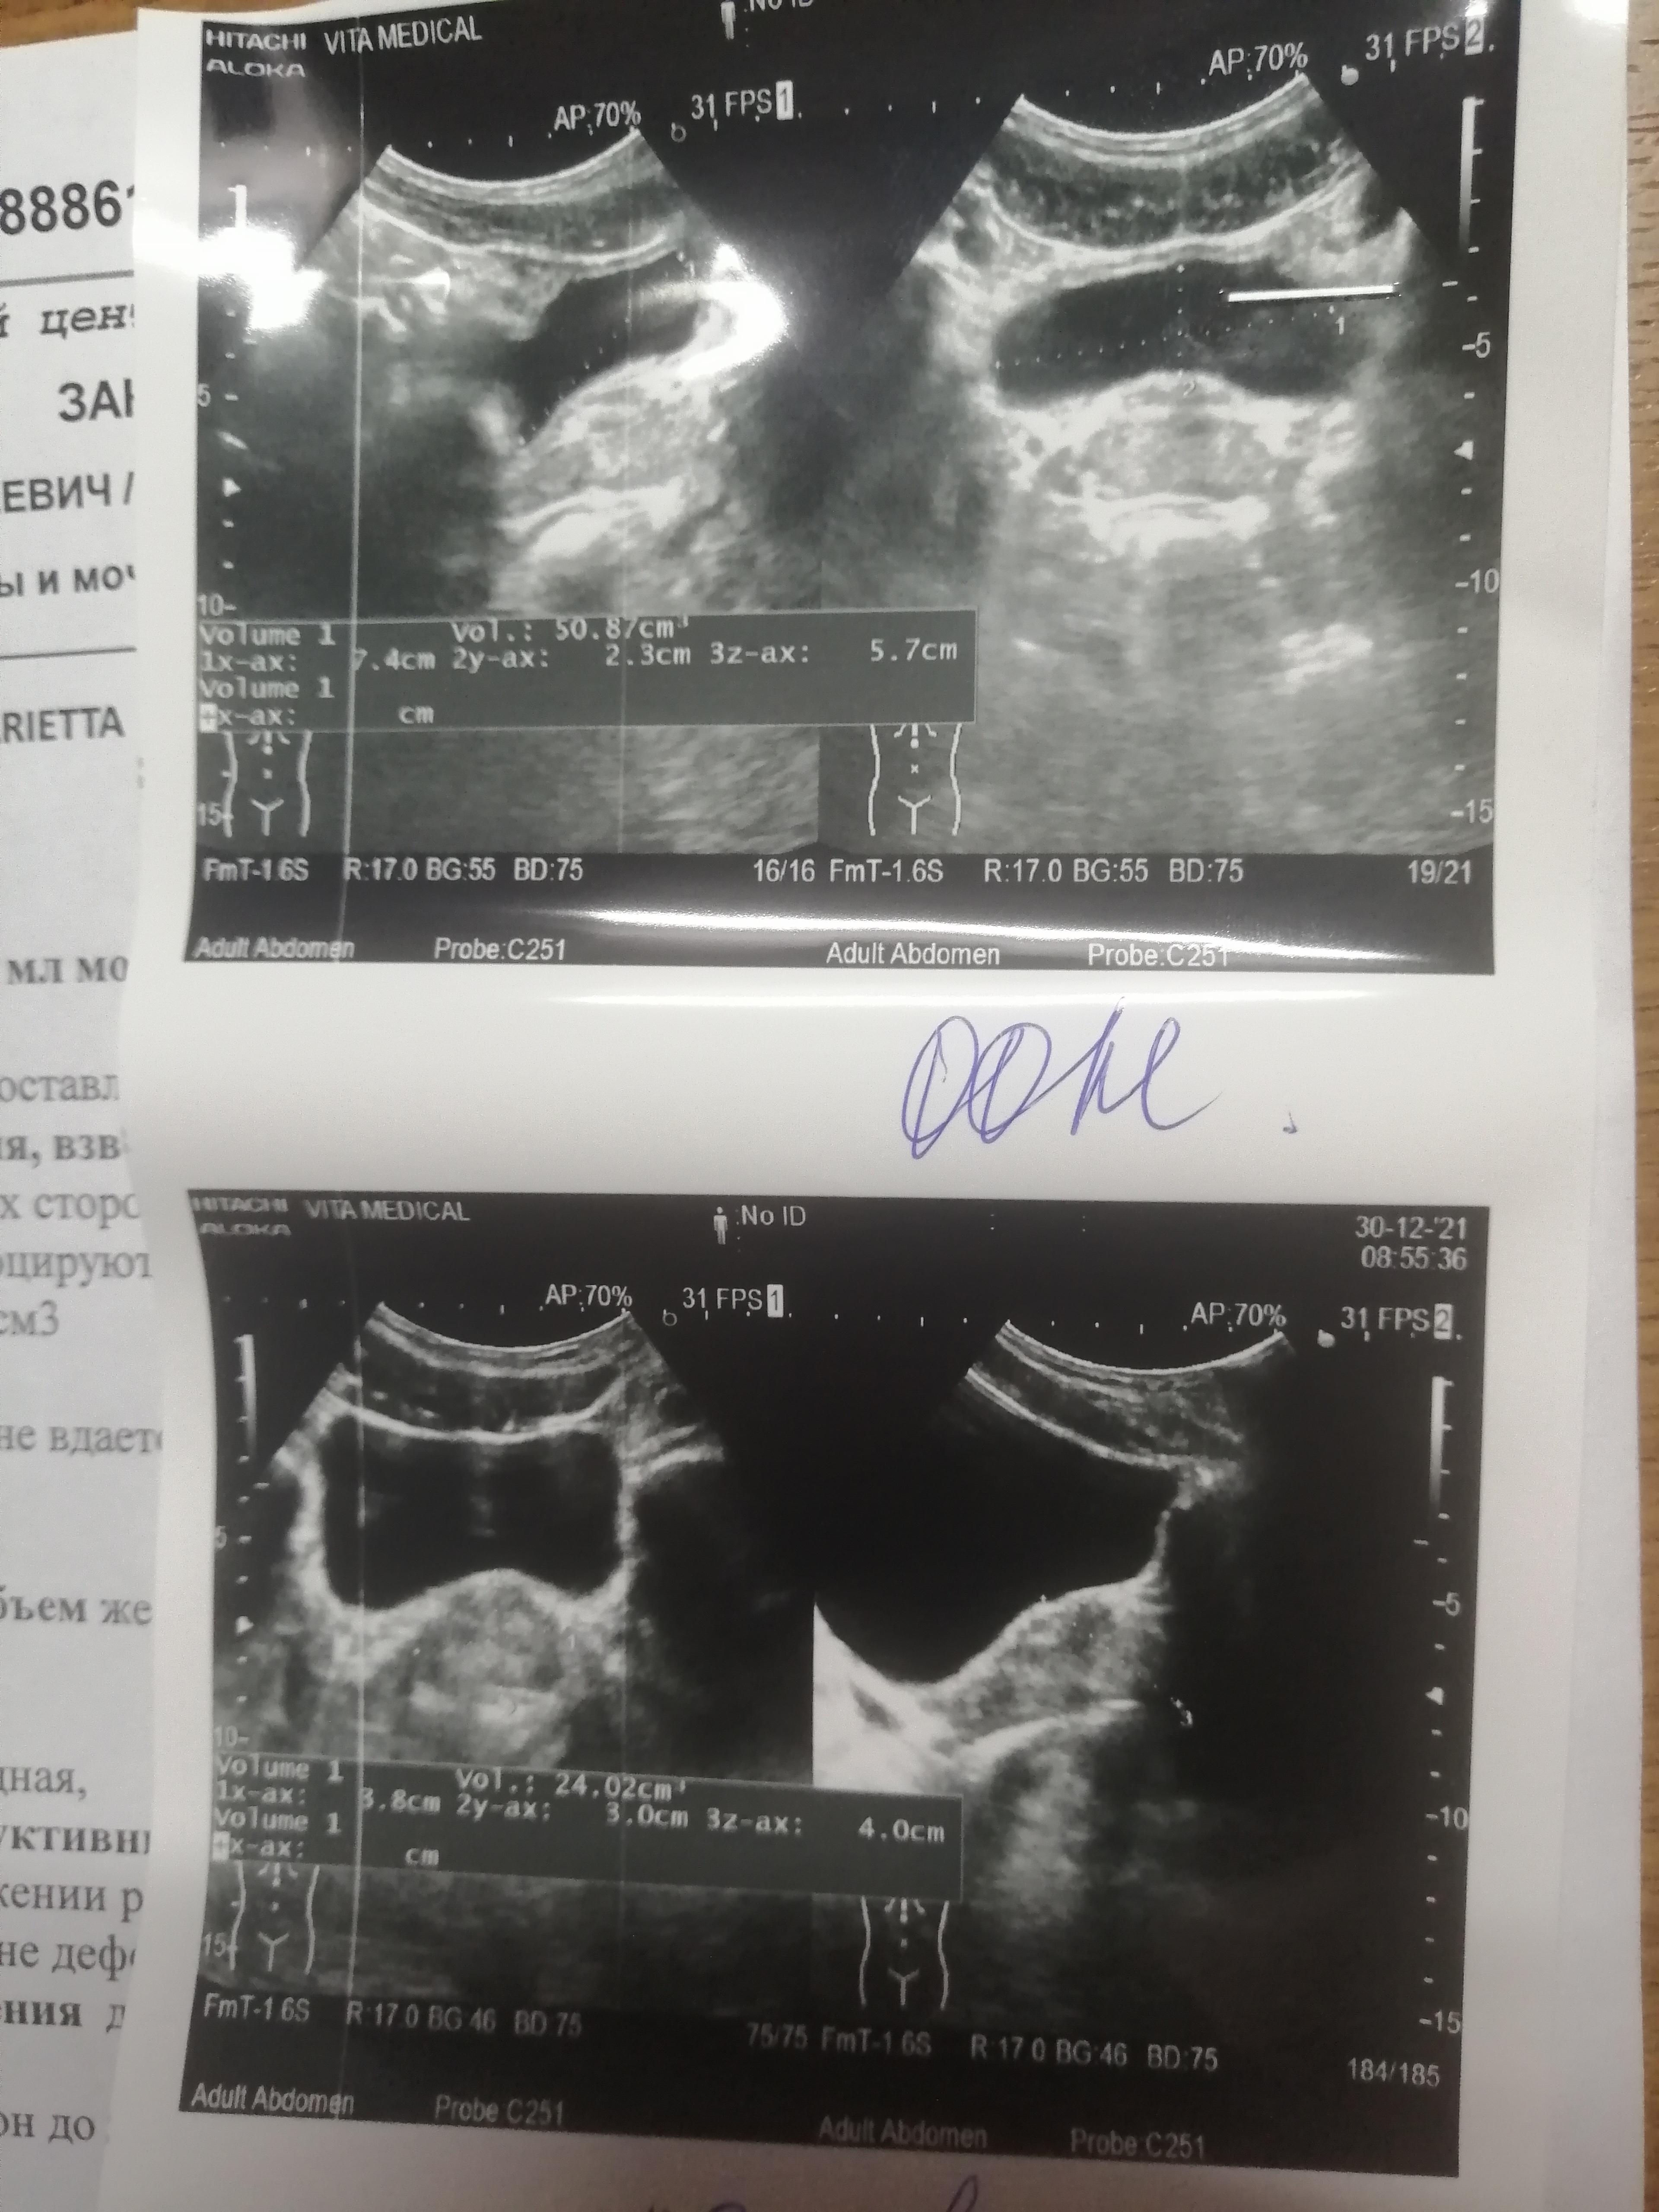

Здравствуйте, появились боли при мочеиспускании и боли в заднем проходе, в промежности. Я сходил на узи, объем простаты 24 см 3, толщина целых 4 см. Это же не норма в моём возрасте, мне всего 27 лет. Но в заключении узи норма во всем, ни воспаления, ни чего то ещё. Но в заднем проходе сильно болит и сжет. Был у практолога, он сказал что нет патологии по его части. Скажите, что с размерами простаты, они же сильно увеличены и отклоняются от нормы?

Здравствуйте! Безусловно, проблема есть, учитывая жалобы и наличие остаточной мочи.Вы уже были у проктолога, теперь можете посетить уролога очно. Вам составят план дальнейшего обследования и лечения. Удачи!